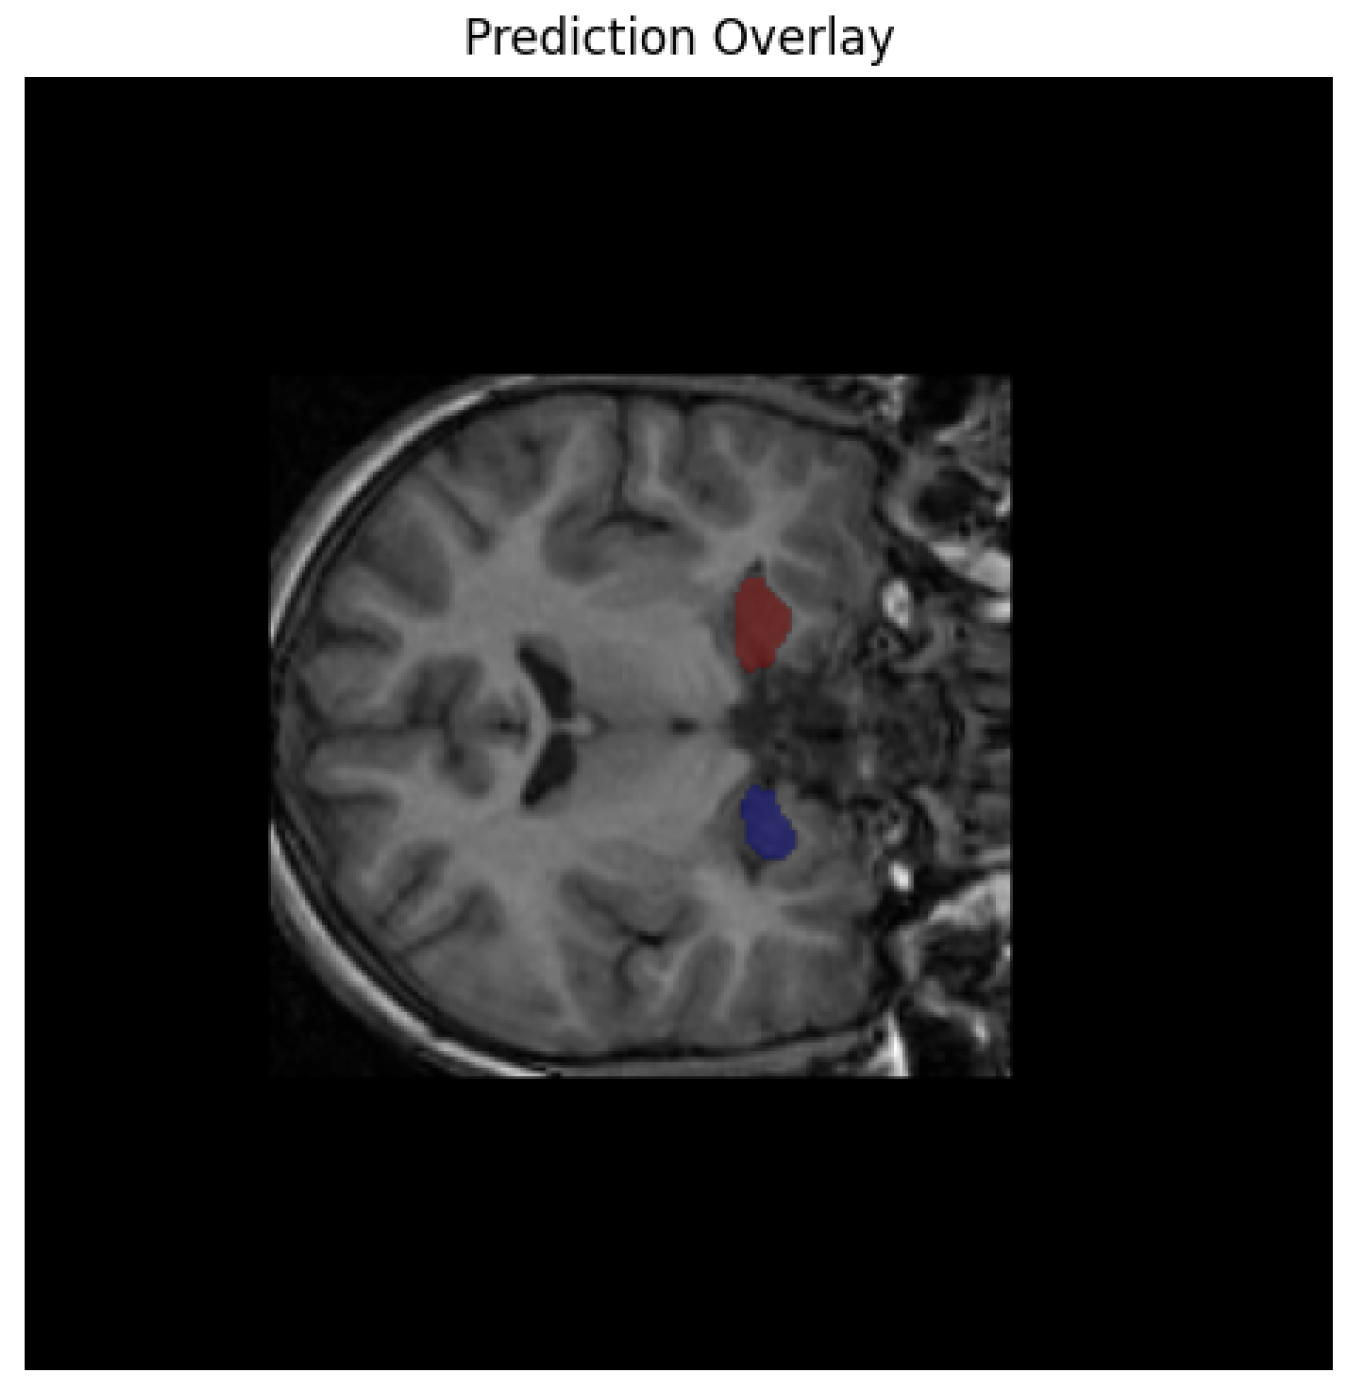

Following segmentation, we conducted extensive post hoc analyses to identify individuals at risk of early neurodegeneration or accelerated brain aging. Using the derived hippocampal volumes, we flagged cases where the total volume fell below a conservative threshold of 5000 mm3 in subjects under the age of 16—an early atrophy marker. Additionally, the brain-age gap was computed as the difference between predicted biological brain age (derived from a regression model trained on hippocampal volume) and chronological age. A gap greater than 5 years was used to define accelerated aging. Subjects who met both criteria (low volume for age and high brain-age gap) were designated as high-risk. This criterion is supported by prior brain-age literature, where such deviations have been shown to correlate with cognitive decline and elevated risk of neurodegenerative progression [35]. While this threshold was originally validated in adult populations, its use here reflects a conservative and translational approach for detecting atypical neurodevelopment in younger cohorts as shown in Figure 4.

Figure 4.

Model’s predicted overlay results.